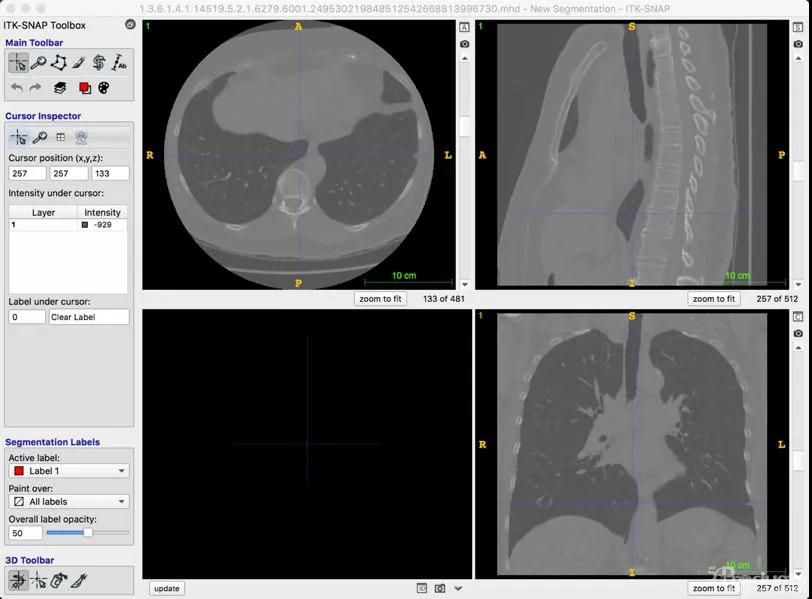

一、AI诊断医学影像,可能被用于疾病初筛

而且钟南山院士等多名专家也介绍了,此次冠状病毒肺炎在发病初起,血常规检测结果几乎没有什么有价值的线索,但是医学影像方面会有异常,由于影像诊断不是量化指标,很难像血结果那样指向明确,人工判断有一定的难度,而且也如钟院士所言,冬季流感本来就高发,如果血液检测没有定量的结果,那么仅靠人工进行影像学的筛查,来判断是否需要进一步确诊,可能会带来一定不确定因素。

人工智能在处理医学影像方面这些年来的进展还是相当不错的,2018年谷歌著名的AI女神李飞飞就曾经发表过一篇针对胸片影像进行深度学习检测的论文《Thoracic Disease Identification and Localization with Limited Supervision》(下载地址:https://arxiv.org/pdf/1711.06373v6.pdf)

其模型工作原理也比较简单,先用Resnet进行特征提取,接下来通过全卷积网络进行分类,输出每种分类的得分,再使用多实例学习来学习多种类型图像,最后输出 图像类别以及对应区域的位置。而且在医疗影像处理方面,国家大厂也是成绩斐然。比如在前年的肺结节检测大赛 (LUNA16)上,阿里云 ET 就在1186 个肺结节(75% 以上为小于 10mm 的小结节)的样本中, 在 7 个不同误报率下发现的肺结节平均成功率达到 89.7%。(注:LUNA大赛中使用召回率,是指在样本数据中成功发现的结节占比,这里使用成功率替代),下图显示了 ET 在不同误报次数下的召回率情况。

在模型结构设计上,ET 针对医学影像的特性,采用多通道、异构三维卷积融合算法、有效地利用多异构模型的互补性来处理和检测在不同形态上的肺结节,提高了对不同尺度肺结节的敏感性;同时使用了带有反卷积结构的网络和多任务学习的训练策略,提高了检测的准确度。

而去年年末,国内顶级AI实验室腾讯优图,也将医疗 AI 深度学习预训练模型 MedicalNet (Github地址:https://github.com/Tencent/MedicalNet)正式对外开源,笔者看到这也是首个开源的能处理3D医学影像的深度学习框架。

python train.py --gpu_id 0

虽然受时间限制,笔者还没有跑完训练脚本。根据Github上的资料显示,MedicalNet 提供的预训练网络可迁移到任何 3D 医疗影像的 AI 应用中,包括但不限于分割、检测、分类等任务。尤其值得一提的是,MedicalNet 特别在小数据医疗影像 AI 场景,能加快网络收敛,提升网络性能,这个特性比较本次疫情确诊样本相当稀缺的情况。